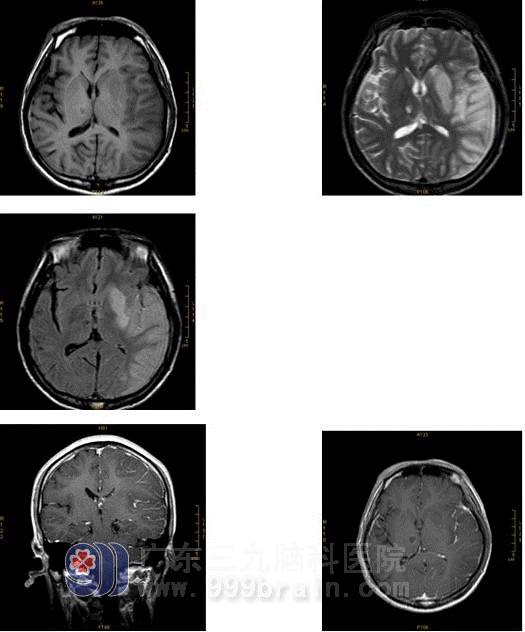

Magnetic resonance showed:

Blood supply section of left brain had lots of infarction, two sides of thalamencephalon had infarction, MRA showed his left brain had artery emphraxis.